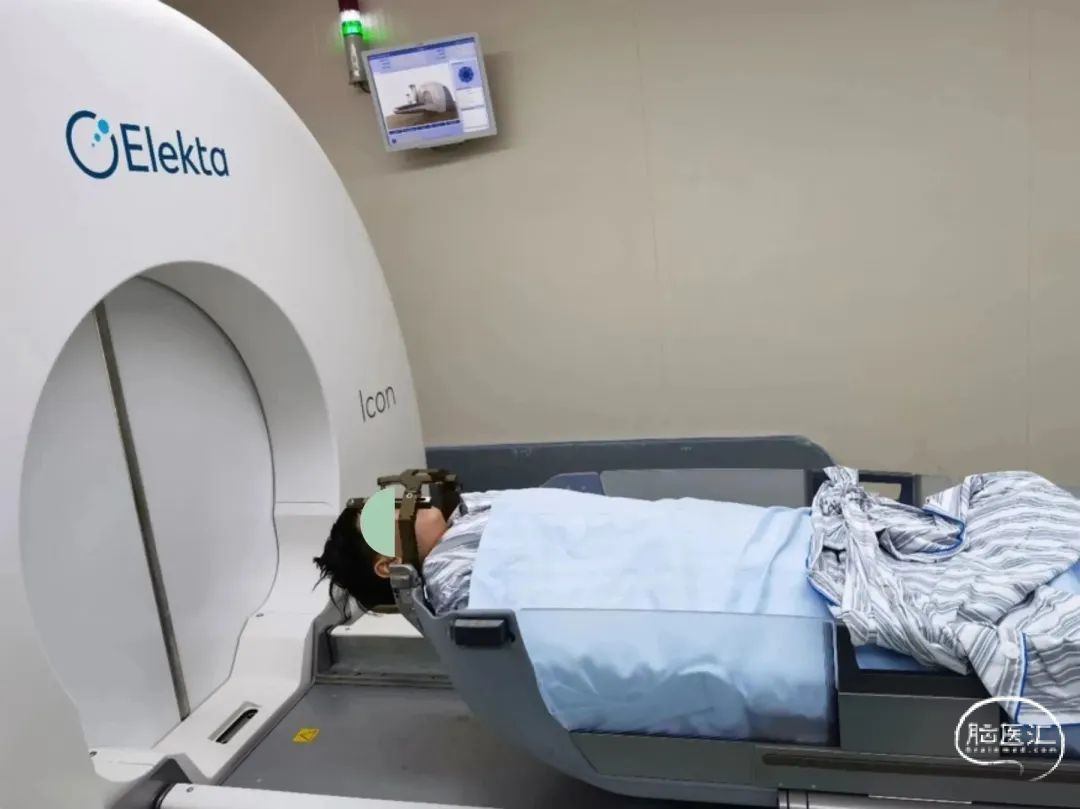

将患者摆位至伽玛刀机器上,进行照射。

总照射时长:75.6分钟

完成治疗,拆除头架。

有症状的脑转移瘤患者无论接受何种全身治疗,都应该积极进行局部治疗(放射外科/放射治疗/外科手术),不应推迟。对于无症状脑转移且没有全身治疗的患者,除小细胞肺癌脑转移之外,1-4个脑转移瘤首选单独的立体定向放射外科;其中,伽玛刀是立体定向放射外科治疗的金标准。对于首发于脑部症状需要开颅手术获取组织病理的或者肿块较大具有脑疝风险的可以选择开颅手术,术后的术腔照射也可以采用立体定向放射外科。

宣武医院伽玛刀中心自Icon伽玛刀启用1周年以来,共完成208次脑转移瘤伽玛刀治疗,始终以科学、开放、合作、严谨、积极的态度,用心、负责任的对待每一位患者。此外,宣武医院神经外科,打破不同技术之间的应用壁垒,无论是单独的伽玛刀治疗、手术切除、激光间质热疗(LITT),还是手术+伽玛刀治疗、全脑放疗+伽玛刀等多种方式联合治疗方案,熟练掌握脑转移瘤的多种治疗技术,将会根据患者的自身具体情况,个体化选择最佳治疗方案。